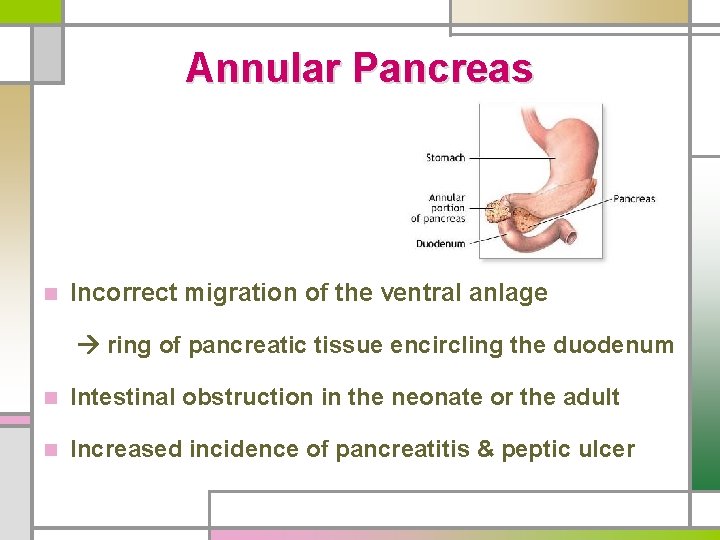

Annular Pancreas n Incorrect migration of the ventral anlage ring of pancreatic tissue encircling the duodenum n Intestinal obstruction in the neonate or the adult n Increased incidence of pancreatitis & peptic ulcer